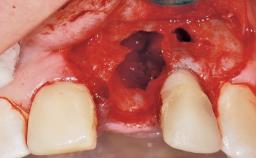

Immediate Placement of an Implant in a Maxillary Left Central Incisor Site

A 33-year-old female patient presented with an upper left central incisor that required extraction after a failed endodontic therapy. The tooth had been traumatized when the patient was a teenager and had undergone several endodontic treatments, including two apicectomy procedures. The patient was in good health and did not smoke. Clinical examination showed that the patient had a high lip line. In full smile, the gingival margins of the upper teeth were visible to the first molars. The gingival margins of central incisors 11 and 21 were only just showing. Examination of tooth 21 confirmed that the tooth was mobile and had hypererupted by 1 mm.

Socket Integrity Damage to one or more bone walls

Bone Volume Damage to one or more socket walls

Soft Tissue Grafting Simultaneous